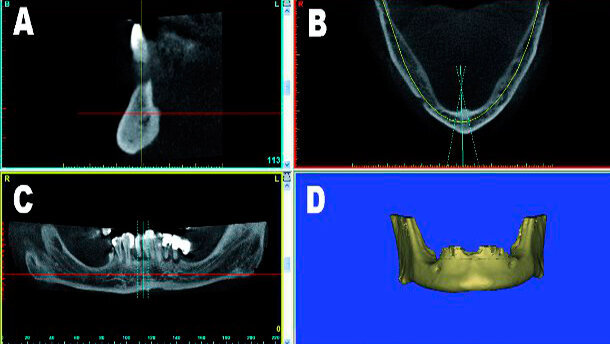

Indipendentemente dal processo di acquisizione dell’immagine, ci sono quattro proiezioni standard che devono essere pienamente apprezzate in fase di diagnosi. Queste includono la sezione trasversale (A), assiale (B), la panoramica (C), e il volume ricostruito in 3D (D) come si vede nella Figura 1.

La sezione trasversale è importante per la valutazione delle lamine ossee corticali vestibolare e linguale, l’osso intramidollare e il posizionamento dei denti all’interno degli alveoli. La proiezione assiale permette di ispezionare l’intera mascella superiore o inferiore, il volume del seno mascellare, la posizione del canale incisale nella mascella e il forame mentoniero nella mandibola. La visione panoramica è un’immagine complessiva di esplorazione, e può essere utile per rintracciare il nervo mandibolare e valutare il pavimento del seno mascellare adiacente la regione nasale.